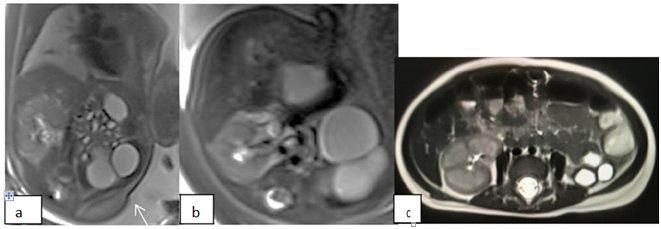

Figure 3a Coronal T2HASTE showing hydroureteronephrosis and thinning renal cortex. 3b: Axial T2 bilateral ureter are dilatation (arrow). 3c: Showing dilatation anterior urethral (arrow) and irregular posterior wall (double arrow).

Gestational age ranged from 19 to 35 eeks. Fetal movement did not alter image quality. We divided into 2 groups of patient between an/oligohydramnios (Table 1) and normal amniotic fluid (Table 2). In an/oligohydramnios diagnosis ultrasound revealed concordant with MRI 2/6 (33,3%) fetuses, 3/6 (50%) MRI gives additional information, 1/6(16,6%) discordant (hypoplasia kidney). In discordant case USG revealed hypoplasia but fetal MRI result agenesis. MRI was performed in 21weeks gestation whereas intensity of kidney is similar with small bowel. Ultrasonography with color Doppler flow easier to visualize renal artery so more accurate to determine agenesis kidney. According to previous journal MRI is to be useful adjunct to US for the diagnosis agenesis kidney.5,9,10 In this case MRI had no significant advantage over US unfortunately the parent refused autopsy (Figure 1). In case ARPKD US is sufficient to see enlargement of the kidney with hyperechoic in medullary kidney and fibrocystic liver (Figure 2), MRI has additional information for looking maturity of the lung. With increasing gestational age the intensity of the lung will increase as well.11,12 In this case fetal MRI examination was performed in 35weeks of gestation, but the lung intensity is still hypointens. An-oligohydramnios prevent growth thoracic cavity therefore maturity of the lung is inhibited which is cannot be seen by US. One case with bilateral hydrouretronephrosis and megacystic based on US, MRI gives additional information a cystic lesion on left kidney. Other case with hydrouretronephrosis and megacystis confirmed by MRI, MRI has additional information dilatation anterior urethra (Figure 3) was proven by MUC (Figure 4). One case with anhydramnios but normal both of kidney the result of US is the same with fetal MRI. The cause anhydramnios is premature rupture of the membrane.